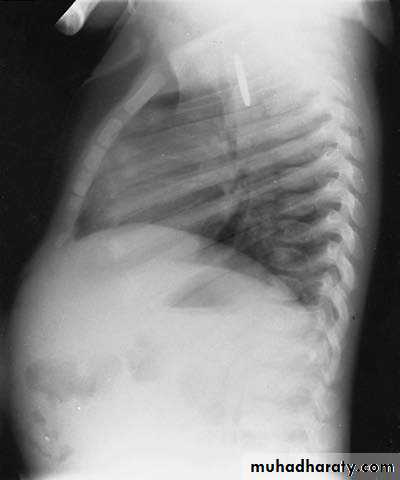

1 y.o infant with effortless vomiting since birth

Growth within normalDx:-Hiatus Hernia(above diaphragm)

Types:-sliding -Roling -Mixed(commonest in pediatrics)

*it’s associated with bleeding—often

-it’s subtype of D.H

Surgery:Fundiplication